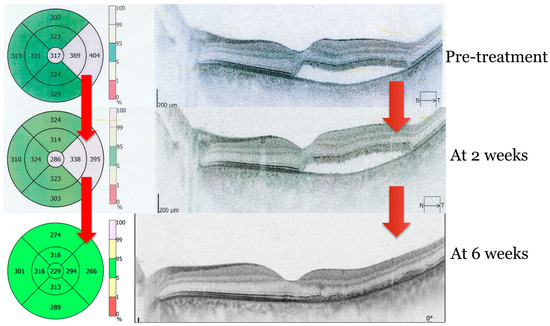

2. Case Presentation